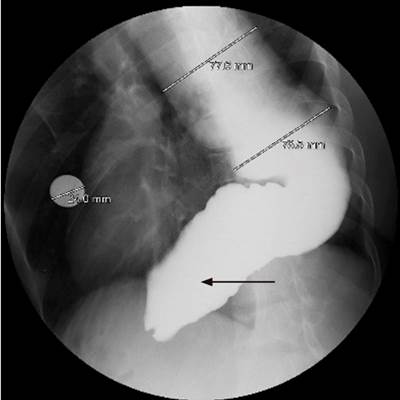

En la esofagogastroduodenoscopia se encontraron restos de contenido alimentario en el esófago, el cuerpo esofágico estaba gravemente dilatado, tortuoso, con angulaciones y la unión gastroesofágica estaba puntiforme, aunque se lograba franquear con dificultad (Figura 3). El esofagograma con bario indicó un cuerpo esofágico gravemente dilatado, con el esófago inferior de patrón sigmoideo (Figura 4).

El esofagograma en un paciente con acalasia en estadio final o megaesófago muestra retención del contraste, en un esófago dilatado, tortuoso, tanto en vista sagital como coronal.